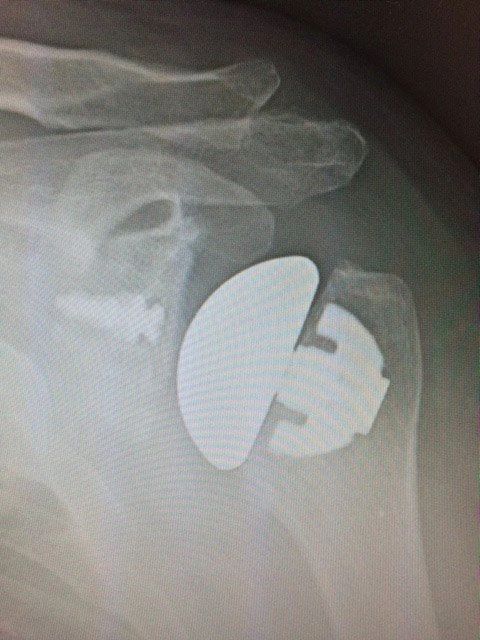

Xray of an anatomic shoulder replacement, showing perfect alignment and no arthritis

2 year follow up on 172 reverse shoulder replacements showing rapid pain relief and slower improvements in range of movement